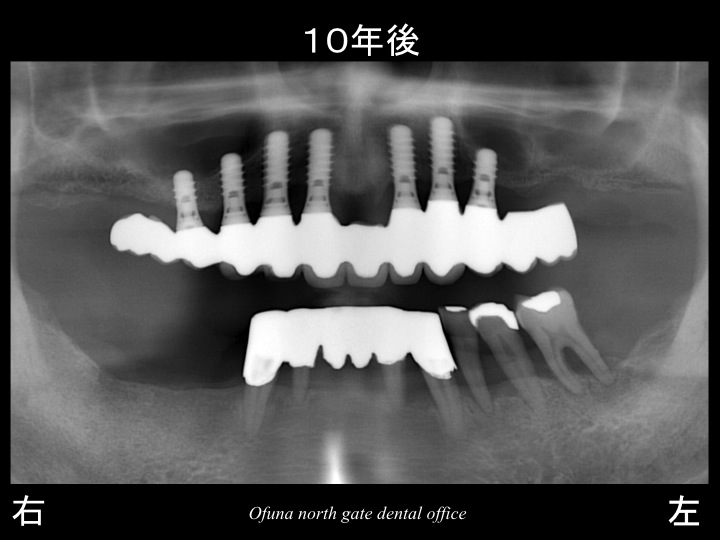

後で治療終了後 約10年のレントゲン写真もでてききますが、

約10年たった現在でも下顎はまったく問題なく維持されています。

徹底した歯周病治療 と患者様の維持管理、メインテナンス(定期検査) が行われれば、このような重度歯周病であっても維持できる可能性はあるのです。